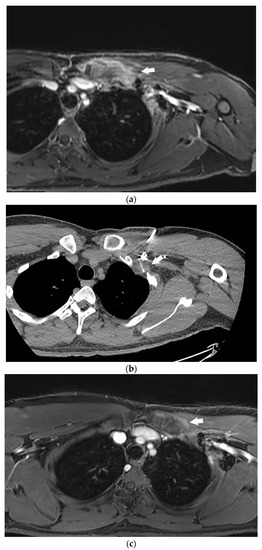

4.3. Cryoablation

- Kujak, J.L.; Liu, P.T.; Johnson, G.B.; Callstrom, M.R. Early experience with percutaneous cryoablation of extra-abdominal desmoid tumors. Skelet. Radiol. 2010, 39, 175–182. [Google Scholar] [CrossRef]

- Havez, M.; Lippa, N.; Al-Ammari, S.; Kind, M.; Stoeckle, E.; Italiano, A.; Gangi, A.; Hauger, O.; Cornelis, F. Percutaneous Image-Guided Cryoablation in Inoperable Extra-abdominal Desmoid Tumors: A Study of Tolerability and Efficacy. Cardiovasc. Interv. Radiol. 2014, 37, 1500–1506. [Google Scholar] [CrossRef]

- Schmitz, J.J.; Schmit, G.D.; Atwell, T.D.; Callstrom, M.R.; Kurup, A.N.; Weisbrod, A.J.; Morris, J.M. Percutaneous cryoablation of extraabdominal desmoid tumors: A 10-year experience. Am. J. Roentgenol. 2016, 207, 190–195. [Google Scholar] [CrossRef]

- Redifer Tremblay, K.; Lea, W.B.; Neilson, J.C.; King, D.M.; Tutton, S.M. Percutaneous cryoablation for the treatment of extra-abdominal desmoid tumors. J. Surg. Oncol. 2019, 120, 366–375. [Google Scholar] [CrossRef]

- Saltiel, S.; Bize, P.E.; Goetti, P.; Gallusser, N.; Cherix, S.; Denys, A.; Becce, F.; Tsoumakidou, G. Cryoablation of extra-abdominal desmoid tumors: A single-center experience with literature review. Diagnostics 2020, 10, 556. [Google Scholar] [CrossRef] [PubMed]

- Bouhamama, A.; Lame, F.; Mastier, C.; Cuinet, M.; Thibaut, A.; Beji, H.; Ricoeur, A.; Blay, J.-Y.; Pilleul, F. Local Control and Analgesic Efficacy of Percutaneous Cryoablation for Desmoid Tumors. Cardiovasc. Interv. Radiol. 2020, 43, 110–119. [Google Scholar] [CrossRef] [PubMed]

- Yan, Y.Y.; Walsh, J.P.; Munk, P.L.; Mallinson, P.I.; Simmons, C.; Clarkson, P.W.; Jayaram, P.R.; Heran, M.K.; Ouellette, H.A. A Single-Center 10-Year Retrospective Analysis of Cryoablation for the Management of Desmoid Tumors. J. Vasc. Interv. Radiol. 2021, 32, 1277–1287. [Google Scholar] [CrossRef] [PubMed]

- Johnston, E.; Alves, A.; Messiou, C.; Napolitano, A.; Strauss, D.; Hayes, A.; Smith, M.; Benson, C.; Jones, R.; Gennatas, S.; et al. Percutaneous cryoablation for desmoid fibromatosis: Initial experience at a UK centre. Clin Radiol. 2022, 77, 784–793. [Google Scholar] [CrossRef]

- Auloge, P.; Garnon, J.; Robinson, J.M.; Thenint, M.-A.; Koch, G.; Caudrelier, J.; Weiss, J.; Cazzato, R.L.; Kurtz, J.E.; Gangi, A. Percutaneous cryoablation for advanced and refractory extra-abdominal desmoid tumors. Int. J. Clin. Oncol. 2021, 26, 1147–1158. [Google Scholar] [CrossRef]

- Vora, B.M.K.; Munk, P.L.; Somasundaram, N.; Ouellette, H.A.; Mallinson, P.I.; Sheikh, A.; Kadir, H.A.; Tan, T.J.; Yan, Y.Y. Cryotherapy in extra-abdominal desmoid tumors: A systematic review and metaanalysis. PLoS ONE 2021, 16, e0261657. [Google Scholar] [CrossRef]

- Kurtz, J.-E.; Buy, X.; Deschamps, F.; Sauleau, E.; Bouhamama, A.; Toulmonde, M.; Honoré, C.; Bertucci, F.; Brahmi, M.; Chevreau, C.; et al. CRYODESMO-O1: A prospective, open phase II study of cryoablation in desmoid tumour patients progressing after medical treatment. Eur. J. Cancer 2021, 143, 78–87. [Google Scholar] [CrossRef]